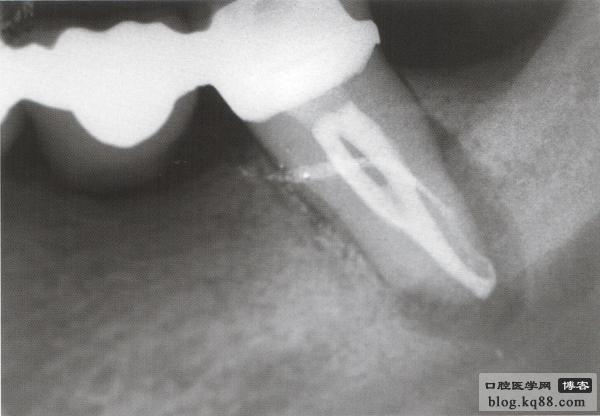

熱牙膠充填后 一年后復(fù)查病變愈合